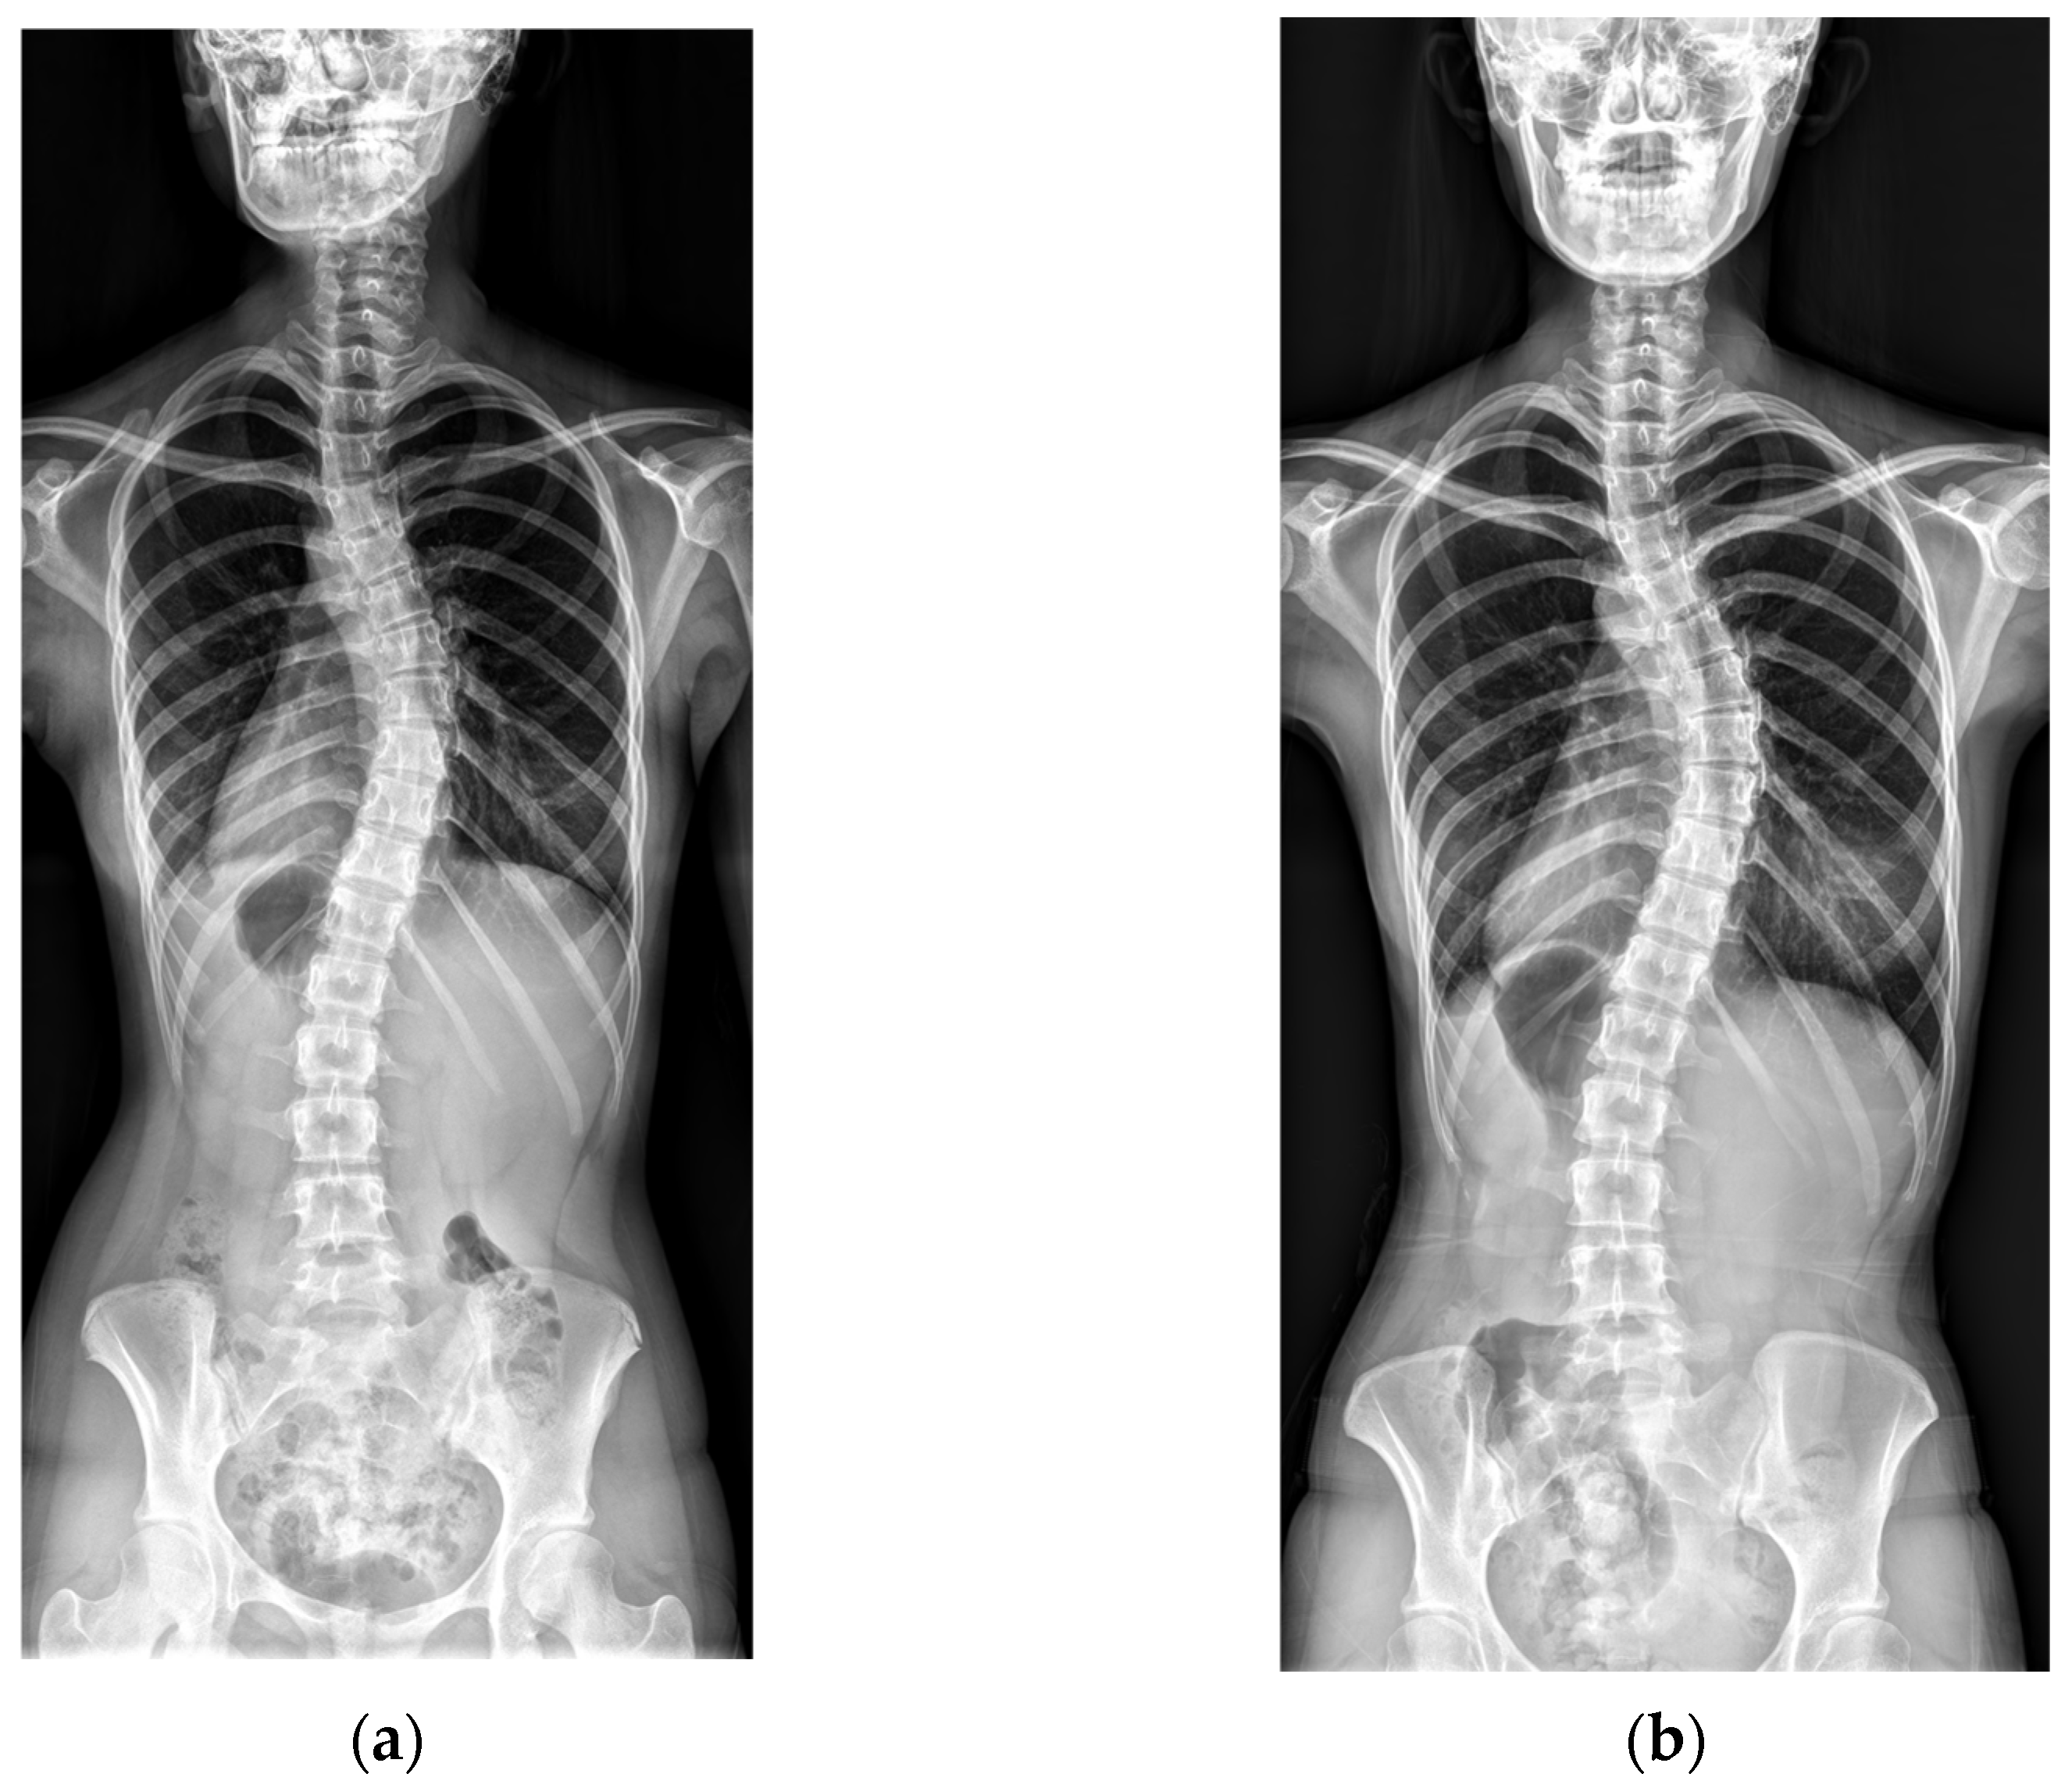

Representative cases from the no-progression and progression groups are shown in Figure 1 and Figure 2.

Figure 1. An example of no curve progression. (a) A baseline radiograph of a 16-year-old female patient with Risser stage V and a Cobb angle of 41°. (b) A final radiograph at age 22, showing Risser stage V and a Cobb angle of 43°.